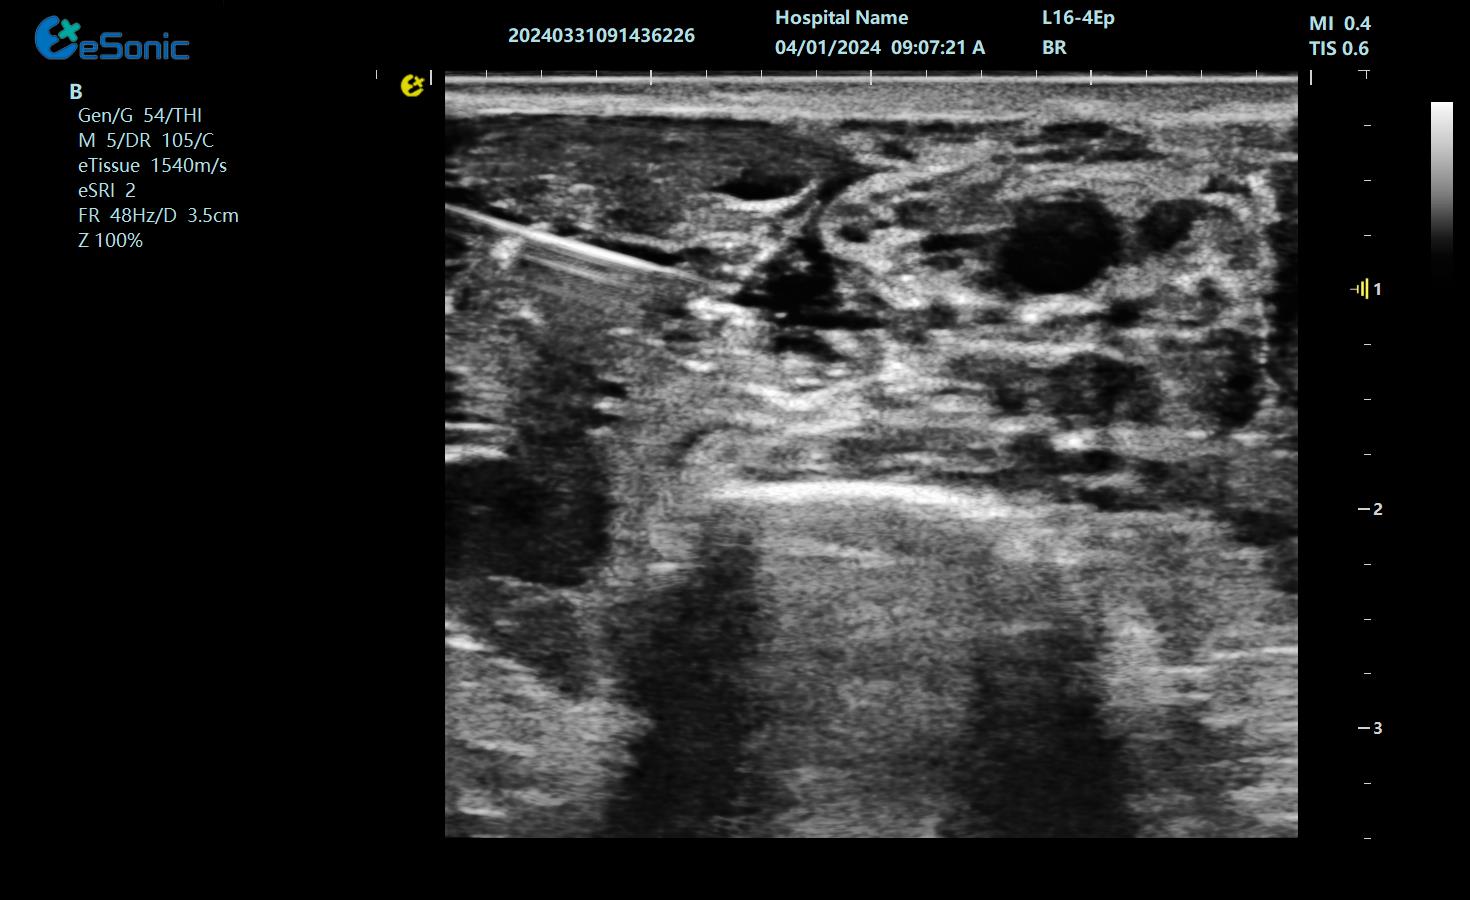

神经阻滞

穿刺智能map